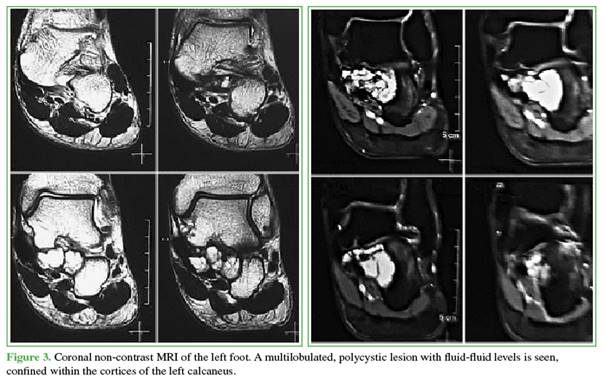

The lateral weight-bearing radiograph of the foot revealed a multilobulated, polycystic lesion confined within the cortices of the left calcaneus (Figure 2). Non-contrast MRI showed an expansile, eccentric lesion with well-defined margins, multilobulated morphology, and internal fluid-fluid levels, measuring 3.3 cm in anteroposterior and transverse dimensions and 2.7 cm in cephalocaudal extension (Figure 3).